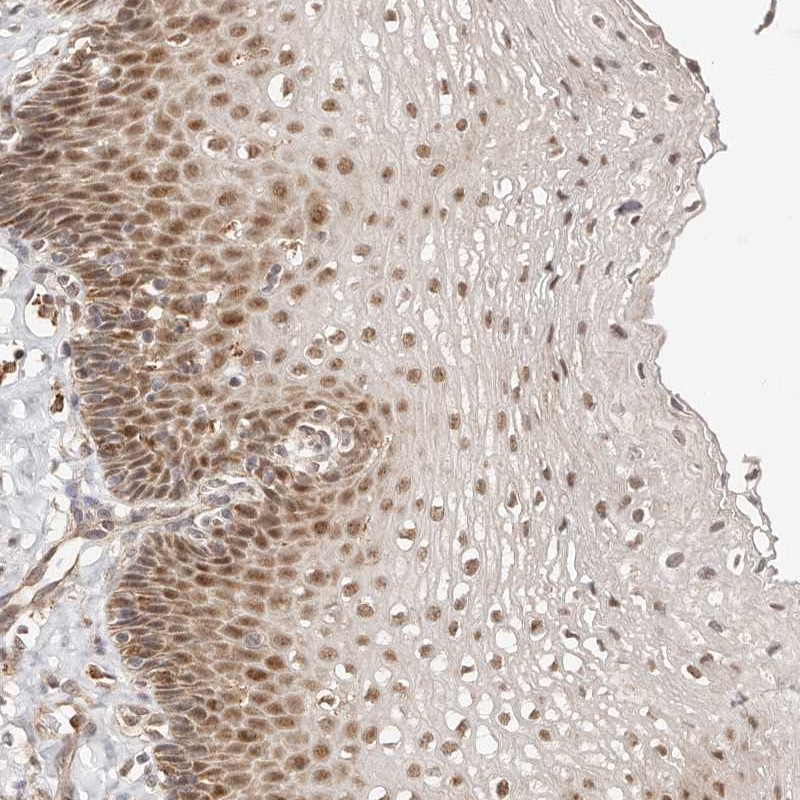

Immunohistochemical staining of human esophagus shows moderate nuclear positivity in squamous epithelial cells.